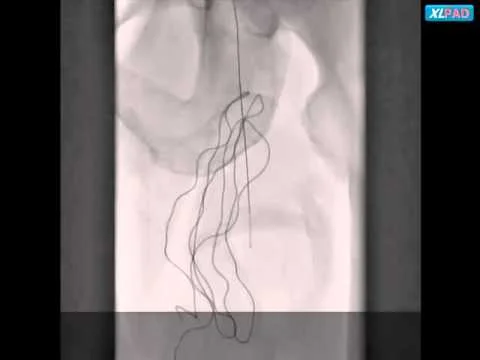

Viance Mid LSFA CTO

Viance Proximal LSFA CTO

Viance RSFA CTO